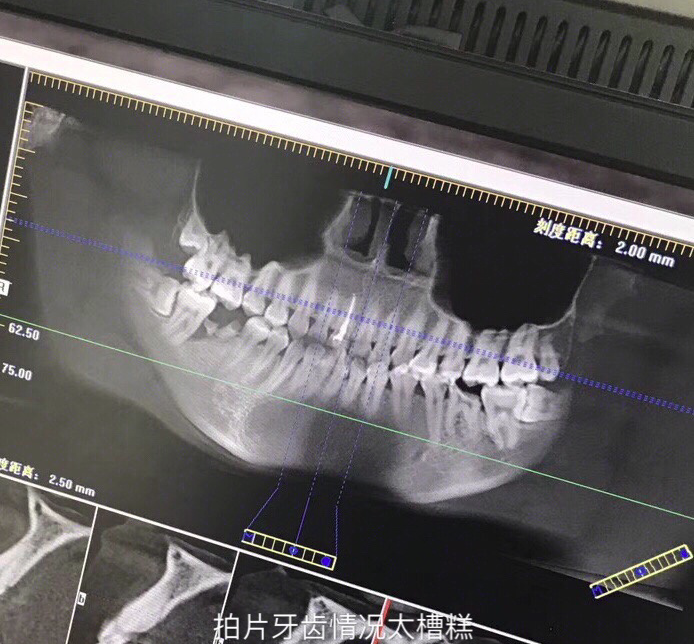

开始矫正年龄:24

牙齿情况:牙列不齐+深覆盖

矫正方式:隐形牙套